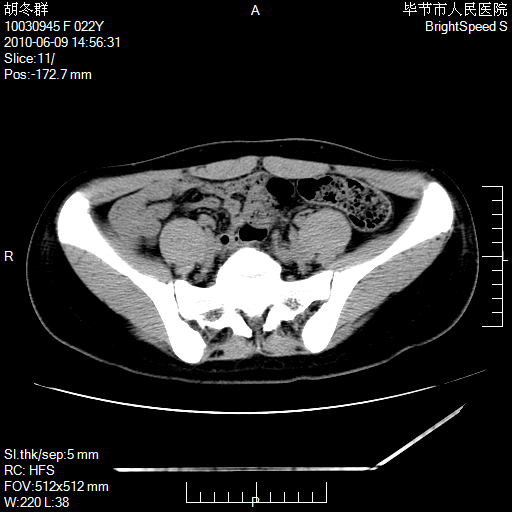

患者23岁,发现腹部包块3月。

我当时考虑重复膀胱,但我错得很厉害,我不明白,囊肿排尿后为什么能到膀胱位置。

盆腔内囊性占位性病变;考虑左侧卵巢囊腺瘤。

有分隔、壁薄,支持考虑左侧卵巢囊腺瘤。

有分隔、壁薄,支持考虑左侧卵巢囊腺瘤。排尿后,膀胱缩小,由于重力作用,肿块下移就到了膀胱位置,很好理解。